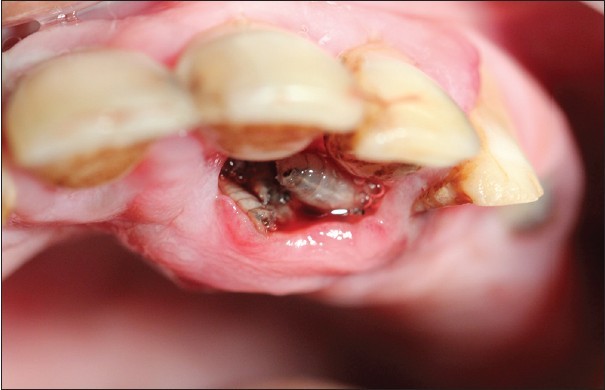

So, Oral Myiasis is a rare disease caused by the Larvae of dipterans. It is reported mostly in developing countries. Myiasis can occur in various parts of our body, not only in the oral region. It can be in the skin, nose, ear, eyes.

Those were some examples of genera. Mostly, it is Chrysomya bezziana (Old Screwworm or Screwworm). It is an obligate parasite; it needs some dead tissue for its species survival, propagation, and reproduction. Its female lays eggs in open wounds, ulcers, scratches, or mucous membranes.

However, the treatment is the surgical removal of larvae. And the result of the activities of larvae is treated after its removal. Turpentine solution help in the extraction of maggots.